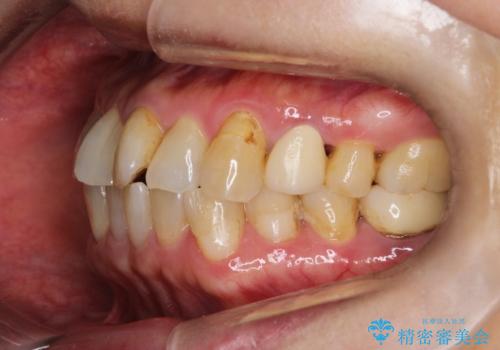

【インビザライン】前歯のガタガタを治したい

- 前歯のガタガタを主訴に来院されました。

上の歯の前突も気になってたため、奥歯の遠心移動も行いながらインビザラインにて治療を行いました。

前歯も下がり満足していただきました。

今回は奥歯の遠心移動とIPRを行って配列しています。